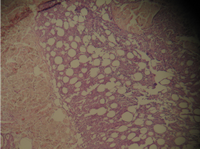

The histologic sections of [patient (b), taken by punch biopsy (4mm) from trunk] revealed superficial and deep perivascular lymphocytic infiltrate with plasma cells in the dermis. Deep lymphocytic infiltration in the fat lobules and in the septa and hyaline necrosis of the fat was present. There was no vasculitis. (Fig 9,10).